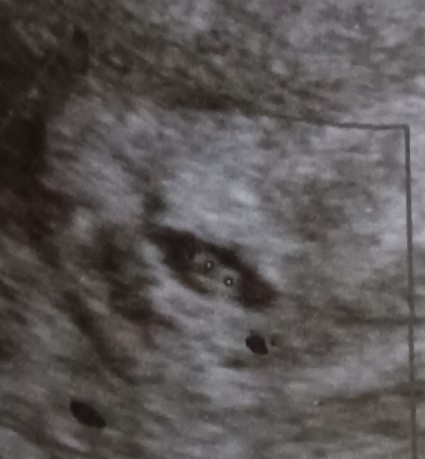

แม่ๆเจอหัวใจน้องตอนกี่สัปดาห์คะ ขอดูรูปอัลตราซาวล์หน่อยคะ😔

6w3dแล้วคะยังไม่เจอหัวใจเลยคะกังวลมากคะ🥺🥲#แม่มีภาสะแท้งคุกครามด้วยคะ#เลือดไหลระหว่างตั้งครรภ์